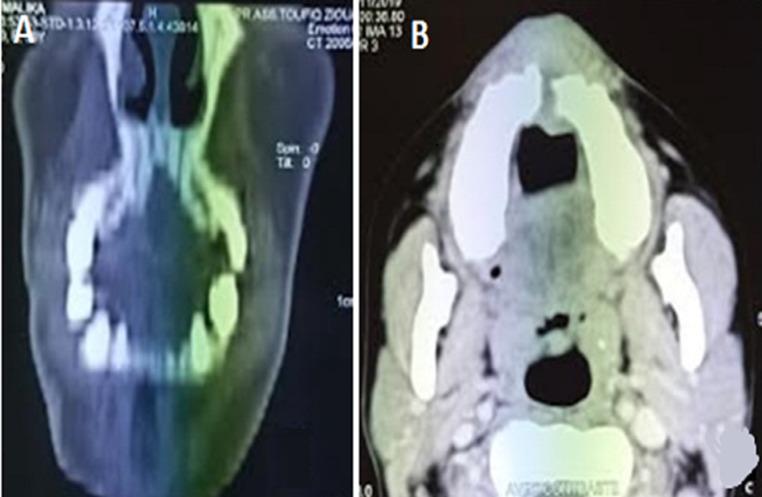

Amelanotic malignant melanoma is an extremely rare and aggressive oral tumor. Herein we report the case of a 42-year-old woman presented with a painful growth in anterior maxillary region. Intra-oral examination showed a non-pigmented exophytic mass occupying the anterior maxillary sector. Incisional biopsy with immunohistochemistry examination revealed a malignant melanoma as it strongly expressed melan A and S-100. Facial computed tomography showed extension to the maxillary bone and hard palate. After thoraco-abdominal computed tomography revealing absence of metastasis, tumor resection was performed respecting 2cm security margin. Oral localization of malignant melanoma is rare especially its amelanotic variant. Lack of pigmentation makes the diagnosis more difficult, usually resulting in treatment delay and making the prognosis even worse. Early detection by histological and immunochemistry examination combined to wide resection are the keys to improving the survival for patients with oral amelanotic melanoma.

无色素恶性黑色素瘤是一种极为罕见且侵袭性强的口腔肿瘤。本文报告了 1 例 42 岁女性,其因前上颌区疼痛性生长就诊。口腔检查显示前上颌区有一无色素的外生性肿块。切开活检结合免疫组化检查显示为恶性黑色素瘤,因为其强烈表达黑色素 A 和 S-100。面骨 CT 显示肿瘤侵犯上颌骨和硬腭。胸腹部 CT 未见转移后,行肿瘤切除术,切缘安全距离 2cm。口腔恶性黑色素瘤的发生部位罕见,特别是无色素型。缺乏色素使诊断更加困难,通常导致治疗延误,预后更差。通过组织学和免疫化学检查结合广泛切除的早期发现是改善口腔无色素性黑色素瘤患者生存的关键。